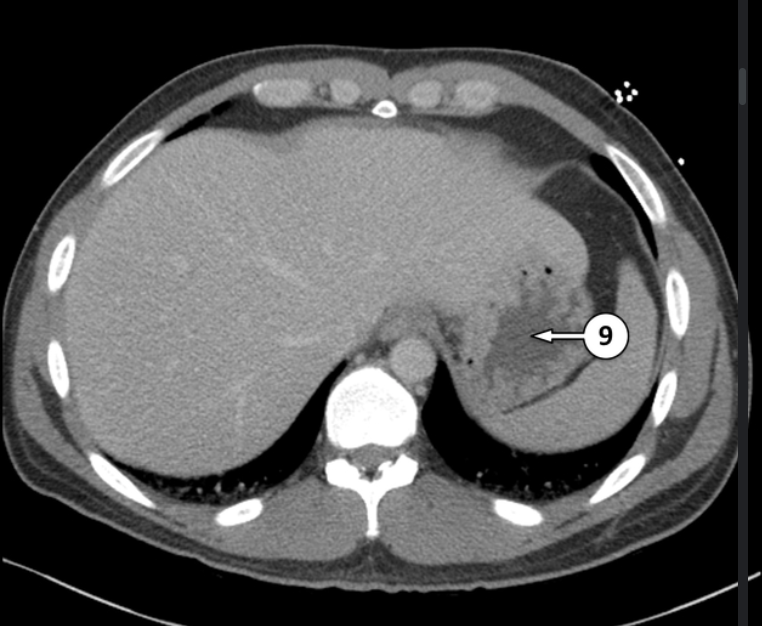

Please label 9

Gatstric fundus